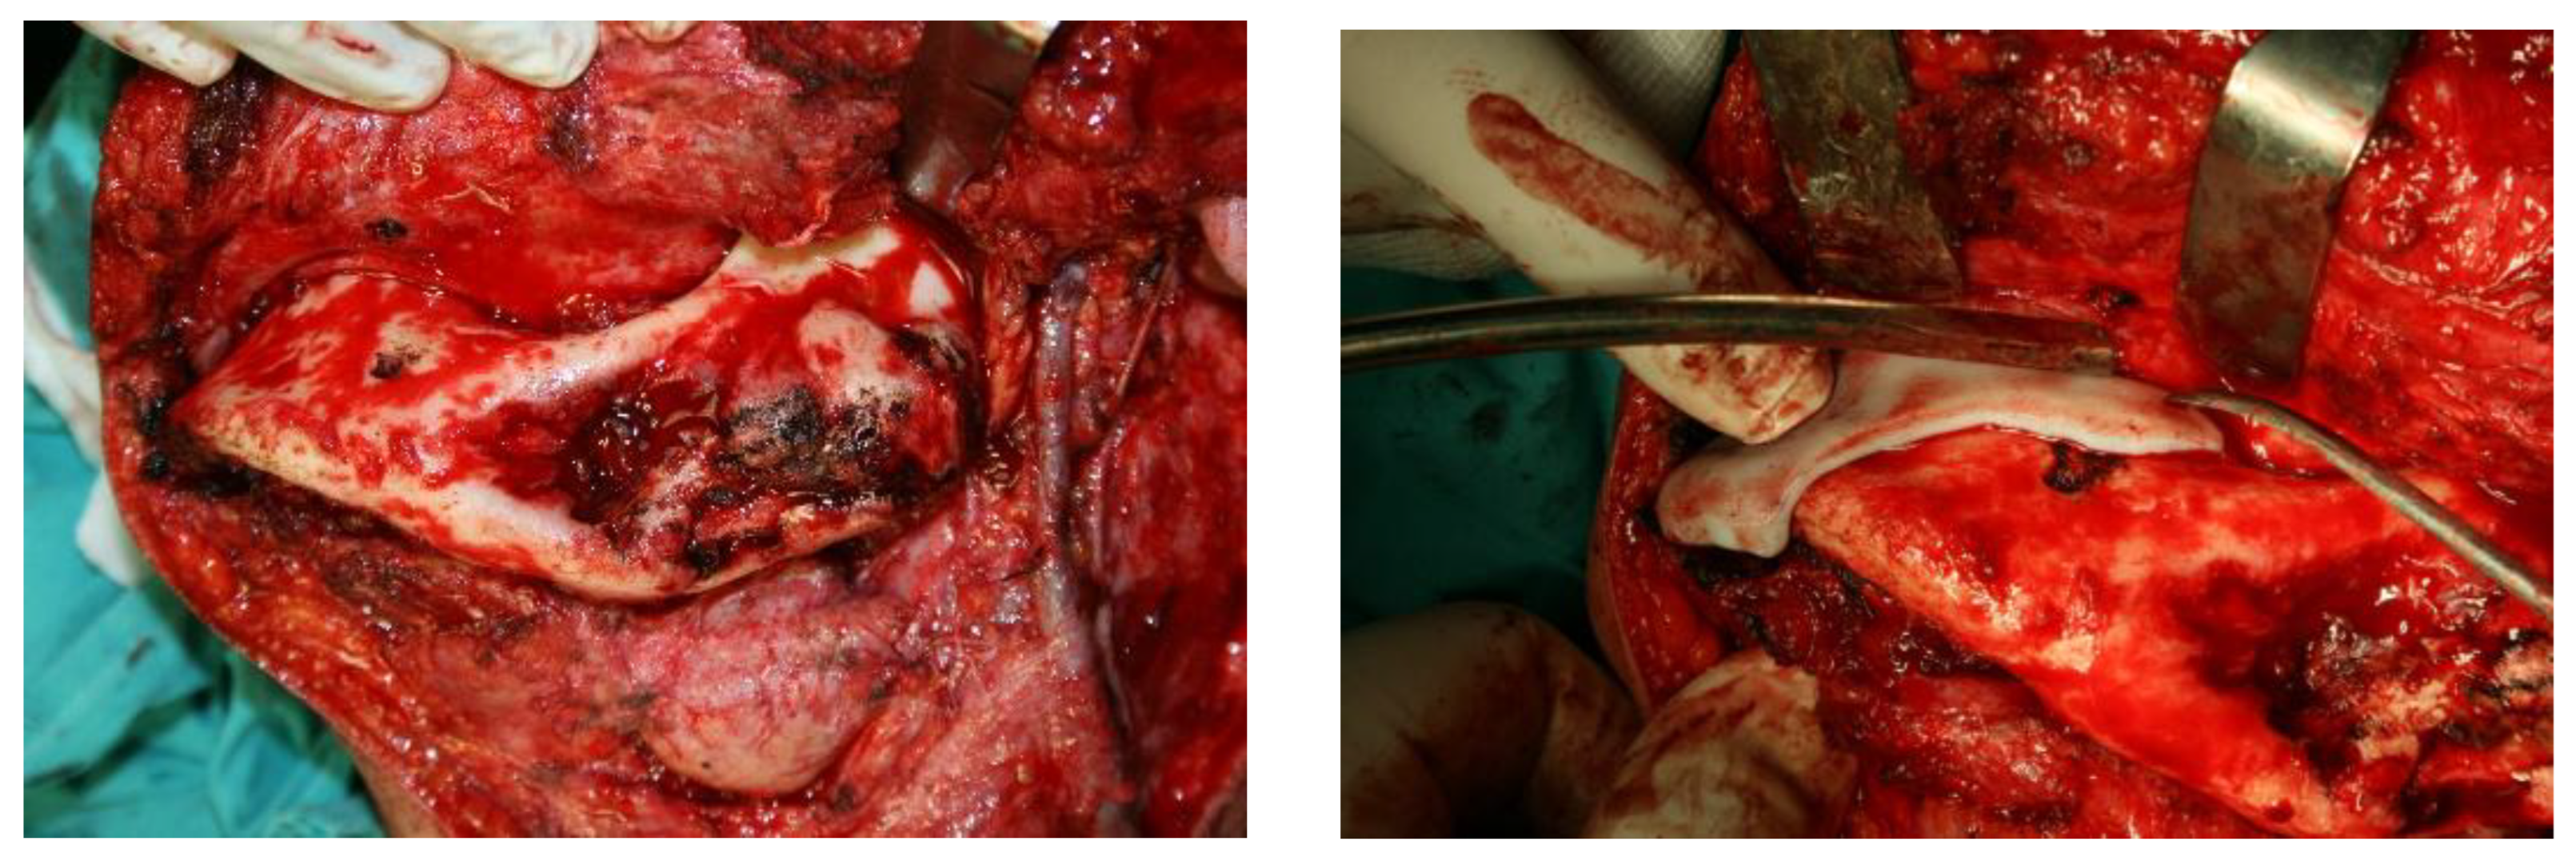

2.2. Methods

- phase 2: Model of the deformed part of the mandible before and after computer-assisted resection

3. Results